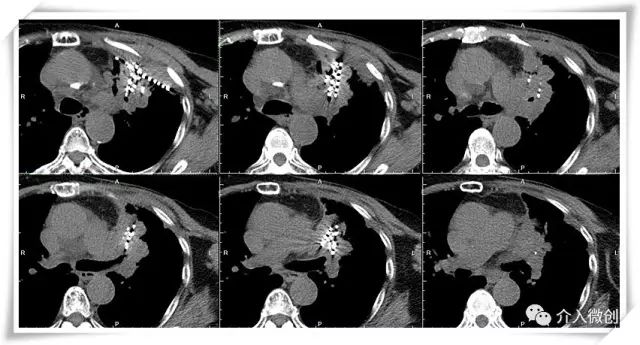

CT引导下放射性粒子植入左侧胸壁病灶及左肺肺门病灶

CT引导下放射性粒子植入左肺肺门病灶